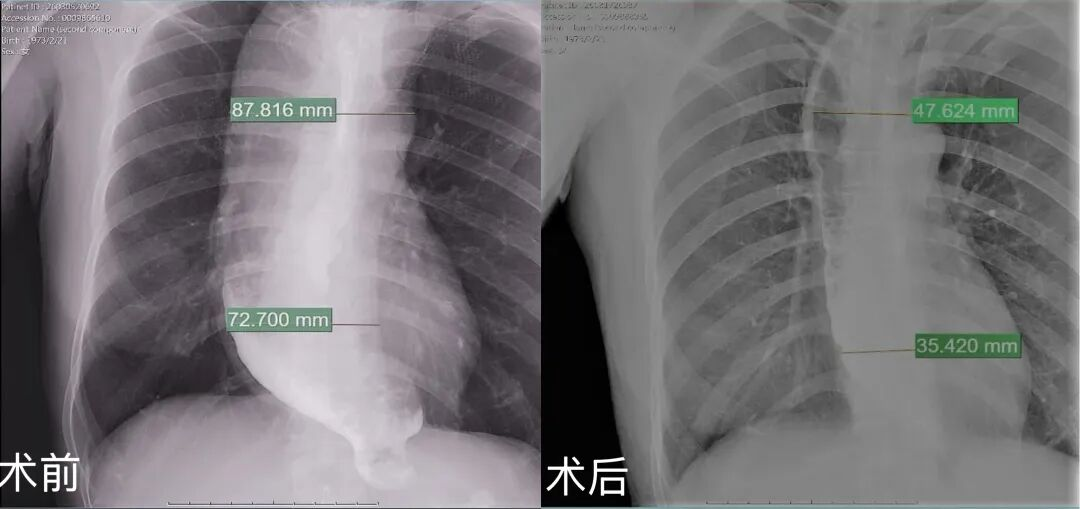

食管上段87.8mm缩小至47.6mm,缩小40.2mm

食管下段72.7mm缩小至35.4mm,缩小37.3mm

术后第二天,喻女士激动地说进食体验有了翻天覆地的变化。此前那种“堵在胸口”的梗阻感完全消失。术后3天能进食,第四天复查食管造影,显示造影剂顺利通过贲门,食管扩张较术前明显改善。术后观察无特殊不适。